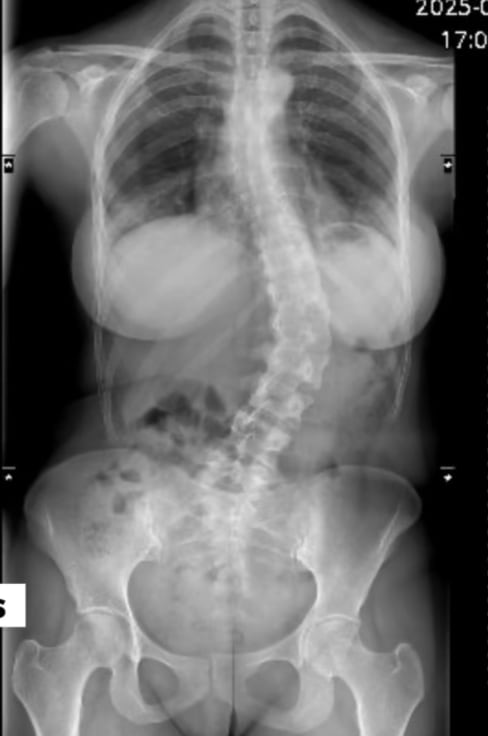

A través de sus redes sociales, Rodríguez contó que su columna presenta una curvatura de más de 40 grados, situación que con los años le ha provocado fuertes crisis de dolor que incluso le han impedido caminar en algunos momentos.

Según explicó, la operación consistirá en colocar dos barras de titanio para alinear la columna. Posteriormente, esta se fusionará en un solo hueso, por lo que dejará de ser flexible y su cuerpo deberá adaptarse a la nueva condición, un proceso de recuperación que puede tardar varios meses.

Según recordó, su escoliosis fue detectada cuando tenía 15 años, luego de que una amiga notara que una de sus caderas estaba más arriba que la otra.